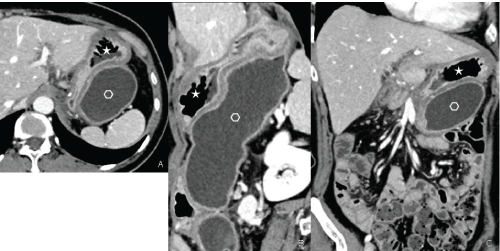

Figure 3: Contrast enhanced CT: Gastric duplication Axial plane (A), sagittal (B) and coronal (C) reconstructions showing the presence of two distinct cavities: Normal gastric cavity (star); duplication cyst (empty hexagon) with tubular morphology. View Figure 3